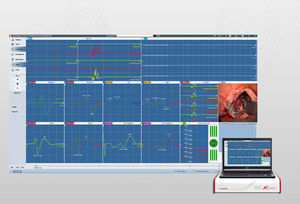

... automáticos es fácil elaborar un informe de PSG según los criterios de la AASM. Para los trastornos neurológicos del sueño, SleepRT™ es el único paquete de software clínico disponible en todo el mundo ...

... datos robusto y preciso para una gran variedad de señales fisiológicas: Cardiovascular Respiratorio Neurológica Electrofisiología Datos in vitro El software IOX2 incluye una amplia gama de analizadores ...

... uso del módulo de software pIOM permite la monitorización del nervio en pelvis menor. Esta nueva tecnología >> ha sido patentada por inomed en toda Alemania. Columna vertebral - Monitorización espinal: El módulo ...